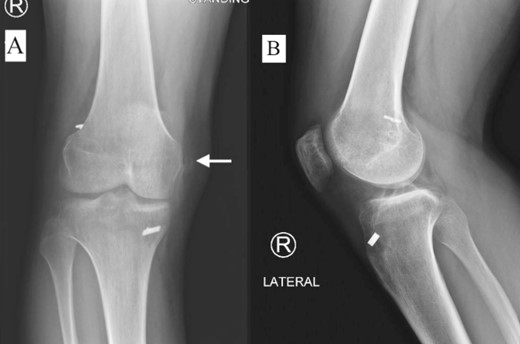

A 23-year-old male veterinarian presented to our out-patient department postright ACL reconstruction with hamstring autograft, PHMM tear by all-inside repair via sMCL pie-crusting technique, and lateral extra-articular tenodesis (modified Lemaire) in June 2023. A preoperative plain radiograph of the right knee revealed no evidence of HO (Fig. 1). No evidence of heterotopic ossification was detected in the right knee on plain radiographs taken 2 weeks postsurgery. (Fig. 2). Five months postsurgery, plain radiographs revealed new bone formation at the medial femoral condyle, precisely where the sMCL femoral origin was located (Fig. 3). The patient was asymptomatic and continued with rehabilitation. Seven months after the surgery, the patient started to complain of pain and clicking sensations when the right knee was flexed beyond an angle of 130°. Magnetic resonance imaging revealed consolidation of the newly formed bone, leading to a diagnosis of HO post-sMCL pie-crusting (Fig. 4). Nine months following surgery, the patient began to feel a bony mass on the medial side of the right knee. A plain radiograph and computed tomography (CT) scan revealed the complete formation of a bone island (Fig. 5). The past surgical history of this patient revealed that he had undergone left knee ACL reconstruction with hamstring autograft in December 2021, which failed and was complicated by a PHMM tear. The patient had presented to our facility for a revision. A revision ACL reconstruction was done using a bone-tendon-bone (BTB) autograft and PHMM tear all-inside repair via the sMCL pie-crusting technique in February 2022. A 2-year follow-up of the left knee, including physical examination and 3D-CT scans (Fig. 6), revealed no symptoms or signs of HO, although the same technique of sMCL pie-crusting was employed. Our patient suffered no head trauma during treatment. Past medical, drug, allergy, family, social histories, and reviews of systems were irrelevant to our case.

Plain radiograph of right knee AP (A) and lateral (B) 5 months postoperative showing initial HO.